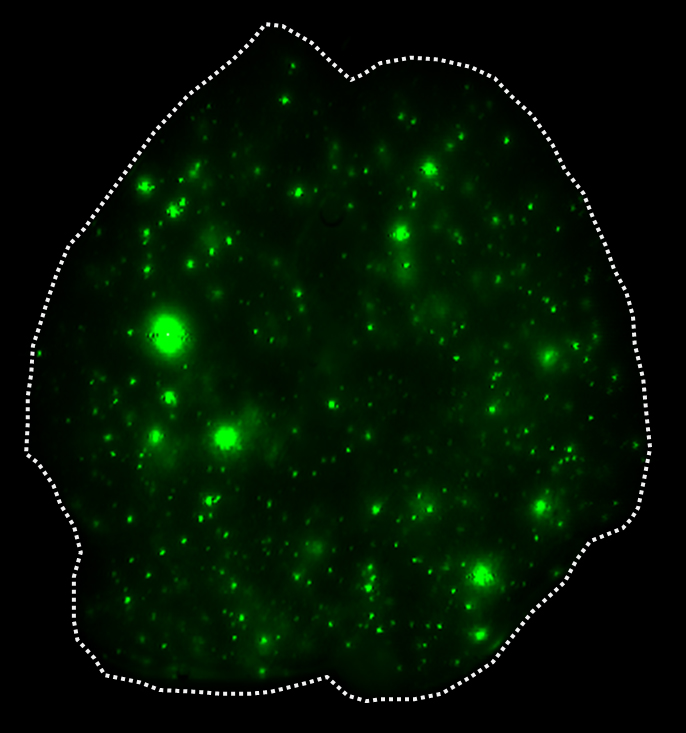

To illuminate the role of exosomes in cancer metastasis, the investigators used patient-derived cell lines of breast cancer that spreads to the lungs and of pancreatic cancer that spreads to the liver. They coupled a fluorescent dye to the fatty membranes of exosomes isolated from each cancer and injected them into healthy mice. There, they observed the exosomes traveling to and fusing with cells in the lungs and in the liver, respectively. The investigators then used the same approach for 28 other cancers, including colorectal, lung, melanoma and pediatric cancers that metastasize to specific organs, such as lung, liver and brain. Exosomes from each cancer reached the organs associated with metastasis. Once there, the exosomes reprogrammed the organ sites that would otherwise be incapable of colonizing cancer to support tumor cell growth.